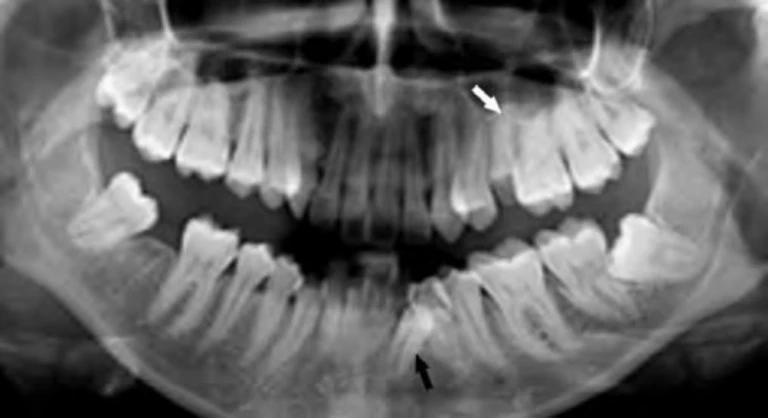

Hình 9D. Mũi tên đen chỉ vào răng nanh hàm dưới hoàn toàn nằm ngoài cung hàm và có thể bị nhổ bỏ như là một phần của kế hoạch điều trị chỉnh nha, mũi tên trắng chỉ vào một răng cối nhỏ thứ hai hàm trên bị sâu răng nghiêm trọng